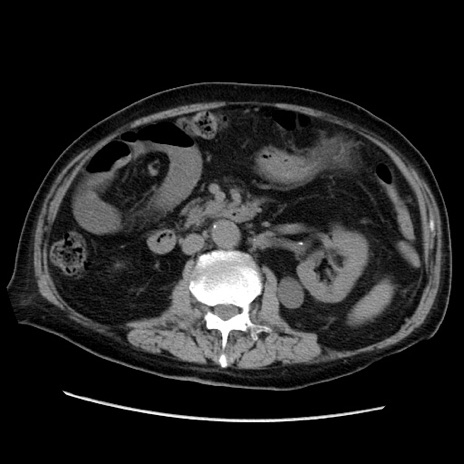

症例21(横断像)

【症例】70歳代男性

【主訴】腹痛

【現病歴】肝硬変・肝細胞癌にてかかりつけの方。約9時間前に食後より腹痛出現。症状が徐々に増悪し、嘔吐出現したため来院。

【既往歴】肝硬変、肝細胞癌(RFA、TACE後)

【身体所見】意識清明、表情苦悶様、BT 36℃、BP 129/78mmHg、P 88bpm、SpO2 97%(RA)、右上腹部から心窩部にかけて圧痛あり、反跳痛なし、筋性防御あり。

【データ】WBC 5800、CRP 0.16